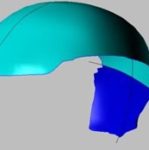

3D model

Protože poškození bylo velmi vážné, rozhodl se výrobce vyrobit protézu ze dvou částí.

Dr. P. Kasprzak vysvětluje – největší protéza zaznamenaná v literatuře měla 400 cm2. V našem případě – 280 cm2. Jedná se o druhý největší případ na světě (samozřejmě ze známých případů).